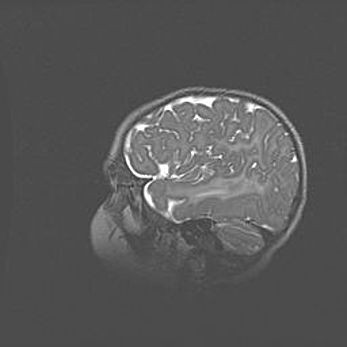

Лейкомаляция с кистозно-глиозной дегенерацией головного мозга.

Возраст: 2 месяца 25 дней

Вес: 6400 г

Окружность головы: 40 см

Срок гестации: 41 неделя

Лейкомаляцию относят к ишемически-гипоксическим повреждениям головного мозга, диагностируемым у новорожденных. При лейкомаляции в головном мозге обнаруживают очаги некроза, возникшие после тяжелой гипоксии и нарушения кровотока. В процессе морфогенеза очаги проходят три стадии: 1) развития некроза, 2) резорбции и 3) формирования глиозного рубца или кисты. Перивентрикулярная лейкомаляция (ПЛ) встречается примерно в 12% случаев среди новорожденных, обычно – у недоношенных детей, причем, частота ее зависит от массы, с которой младенец появился на свет. Наибольшее число малышей страдает лейкомаляцией, если масса при рождении 1500-2500 г.